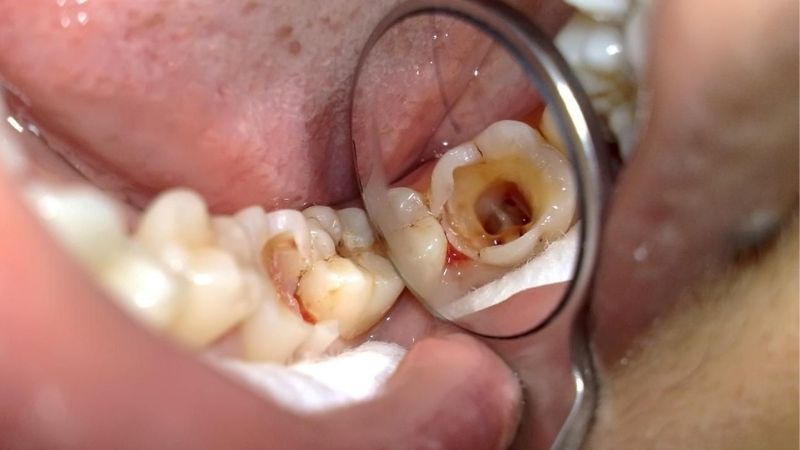

- Mắc một số bệnh lý về răng miệng như: sâu răng, viêm nha chu,… mức độ nặng khiến răng bị mất nhiều, theo thời gian sẽ dẫn đến mất răng cả hàm.

Hình ảnh bệnh nhân bị sâu răng